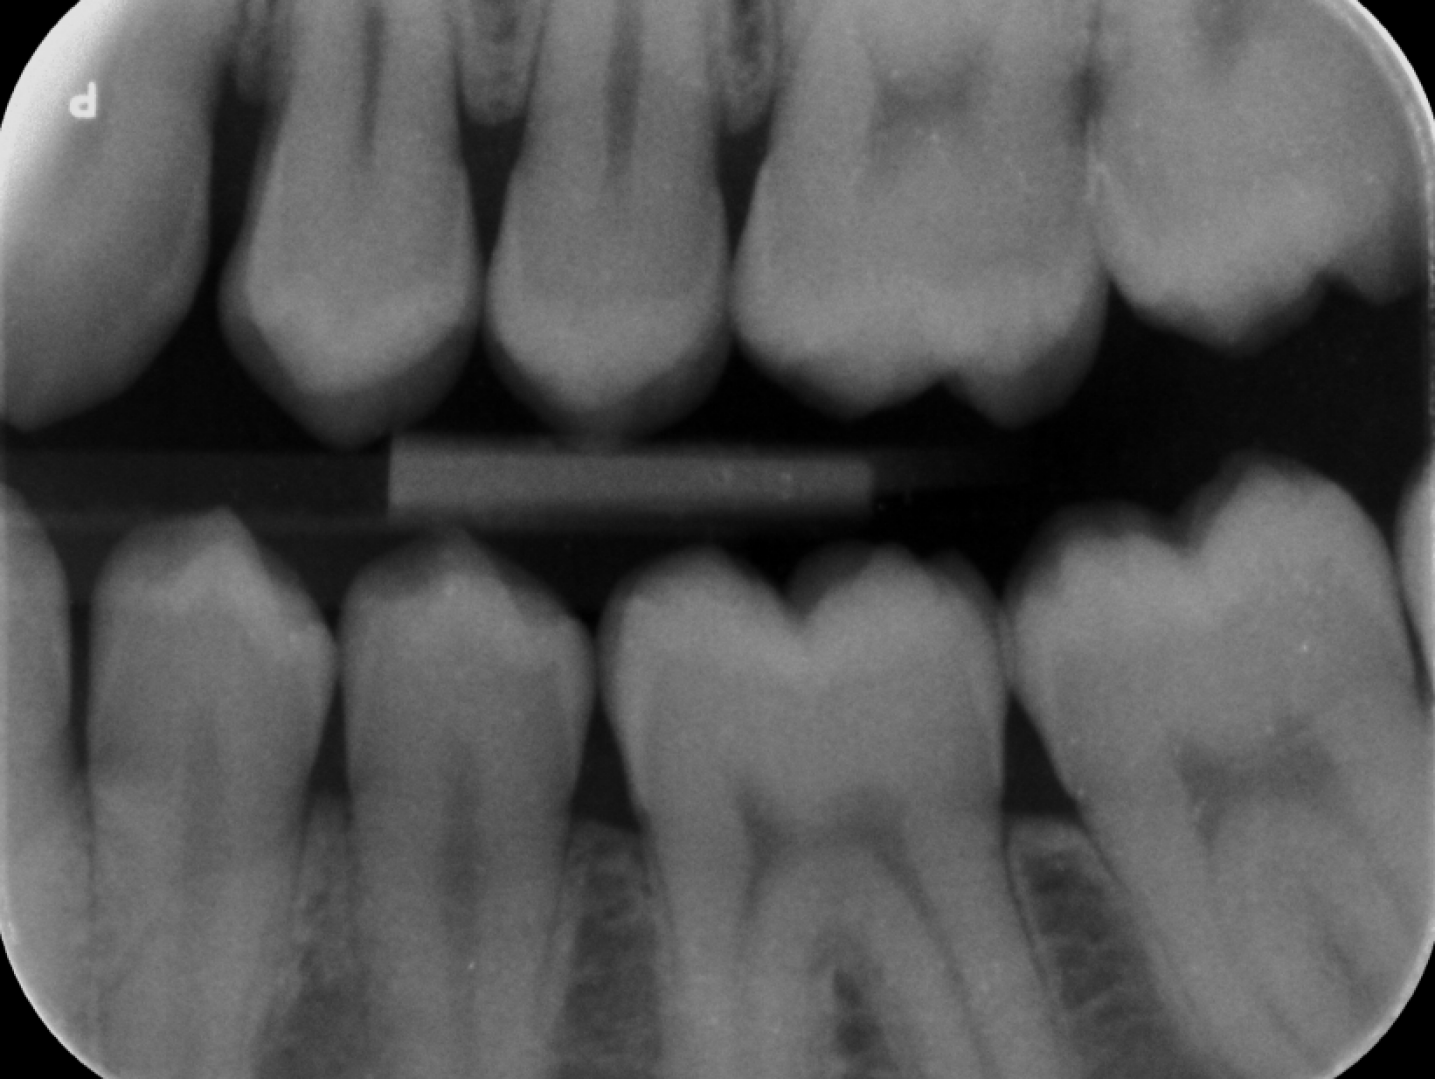

Fig. 3: (a) Input image. (b) - (e) Dental anatomy segmentation results. (f) Ground truth (GT) segmentation mask.

Besides, the performance of the proposed method in dental anatomy segmentation is summarized in Table 2. DentalX achieves mIoU, mDice, and mAcc of 86.3, 92.5, and 94.2, respectively, outperforming other baselines. This is because the segmentation task benefits from the better-learned features of the shared FPN backbone, leading to increased segmentation performance (See Ablation Study). Moreover, as shown in Fig. 3, DentalX produces anatomy masks that are more pixel-accurate than other baselines.